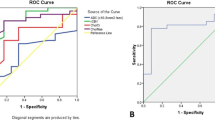

Regarding rCBVt value, at a value more than 1.7, the sensitivity was 96.87% and specificity was 95.24%; more than this value, it is considered HGG (Fig. 4).

Regarding rCBVp value, at a value more than 1, the sensitivity was 87.5% and specificity was 100%; more than this value, it is considered HGG (Fig. 5).

Regarding the Cho/NAA ratio, at a value more than 1.8, the sensitivity was 100% and the specificity was 76.2%; more than this value, it is considered HGG (Fig. 6) (shown in Table 3).

Regarding the Cho/Cr ratio, at a value of 1.8, the sensitivity was 96.9% and the specificity was 76.2%; more than this value, it is considered HGG.

The leave-one-out method, in fact, showed that 76% of tumor masses were correctly reclassified when performing discriminant analysis regarding MRS variables alone and 100% when regarding both MRS variables and rCBV (shown in Table 4).